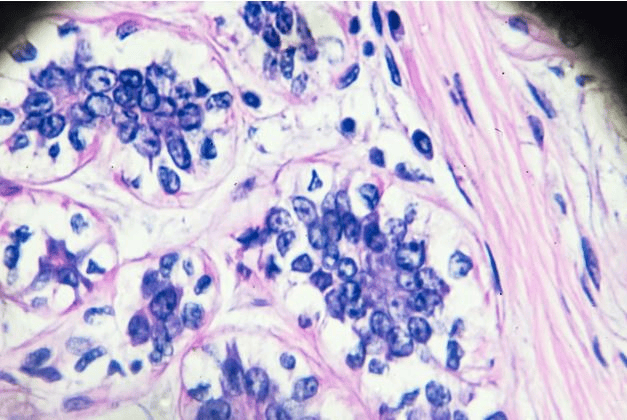

Gjashtë lloje të kancerit; leuçemia, kanceri i tiroides, i gjirit, i endometrit, i zorrës së trashë dhe i veshkave, treguan norma në rritje si tek të rriturit e rinj ashtu edhe tek të moshuarit në gati tre të katërtat e vendeve të anketuara, me lidhje të forta me obezitetin.

Shkencëtarët shpjegojnë se rritja e indit dhjamor mund të shkaktojë inflamacion, të ndryshojë nivelet e hormoneve dhe të prishë metabolizmin qelizor, duke nxitur një mjedis pro-kancerogjen.